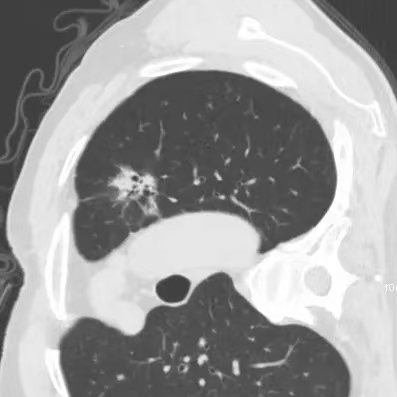

健康直通车: 健康是生命的宝贵财富,也是幸福生活的基石。为了更好地服务广大百姓,传播健康知识,葫芦岛市第二人民医院推出“健康直通车”专题栏目,将专业的医学知识以通俗易懂的方式传递给每一位市民,掌握科学的疾病预防方法,共同构筑健康中国的坚实基石。 什么是肺结节 肺结节是指肺内直径小于或等于3cm的类圆形或不规则形病灶,影像学表现为密度增高的阴影。大于3cm的称肿块。肺结节依其密度不同可分为实性结节、部分实性结节、磨玻璃结节,其中部分实性结节的恶性可能性最大,磨玻璃结节次之,实性结节尤其是小的实性结节结节最可能是良性的。 肺结节的常见病因 1、良性(约90%) 🔸 感染:结核、真菌、细菌性肺炎后遗留的瘢痕; 🔸 非感染:错构瘤(良性肿瘤)、炎性假瘤、血管瘤等。 2、恶性(约10%) 🔸原发性肺癌(如腺癌、鳞癌); 🔸转移性肿瘤(其他器官癌症转移至肺)。 如何根据影像判断肺结节性质 1、依据结节大小判断 🔸小于0.5cm的肺结节绝大多数都是良性的,属于微小结节。即使部分小于0.5cm肺结节是恶性的,但是适当的观察不影响预后。每年复查一次胸部CT就可以。 🔸大于0.5cm持续存在的纯磨玻璃结节,观察6个月,若持续存在,不管有无进展均多数是恶性的,视患者意愿,手术可以立即做也可观察至进展再做,不影响预后。 🔸大于0.8cm的部分实性结节恶性可能性非常大,应积极评估结节边缘毛刺、分叶、胸膜凹陷等征象。 🔸若实性部分大于0.5cm,恶性率显著提高。若在3~6个月随访期间实性部分增大或者总体部分增大,都可以考虑手术切除。而即使小于0.8cm的部分实性结节也需3个月就复查对比。 2、依据肺结节形态 如CT上提示病灶形态不规则、毛刺、分叶、胸膜凹陷、空泡征、血管集束征等,符合恶性肿瘤的征象。 🔸结节与正常肺组织之间界限非常清楚的恶性可能性大。 🔸结节密度不均呈混杂密度或均匀较大纯磨玻璃结节也基本是恶性的。 🔸有胸膜牵拉(不管是肺表面的脏层胸膜还是叶间裂部位的胸膜)的恶性可能性大。 🔸结节有浅分叶、细毛刺,密度较高而与周围肺组织边界不清的恶性可能性大。 🔸磨玻璃或混合磨玻璃结节存在小空洞的恶性可能性大。 🔸影像上似慢性炎表现,而没有炎症相关的其他异常,特别当所谓炎症区域内部或一侧与正常肺组织之间界限非常清楚的基本上是恶性的。 3、从结节发展情况来看 所有随访中增大进展的都需要考虑恶性可能,不进展而持续存在的纯磨玻璃结节也需考虑恶性。 葫芦岛市第二人民医院肺结节诊治中心孙振教授深耕肺结节领域四十余载,凭借对临床实践的执着钻研与深厚积淀,在肺结节精准诊断及鉴别诊断领域形成独到见解。他系统总结海量临床病例,创新性提炼出一套科学化、规范化的肺结节全周期诊疗体系,尤其在早期微小结节的影像特征识别、良恶性风险分层等方面积累了丰富经验,为众多患者提供了精准、高效的诊疗方案。 人民医院·人民名医 孙振 主任医师 三级教授 ·葫芦岛市第二人民医院胸外科主任、肺结节诊治中心主任 ·中国医科大学客座教授 ·原央企总医院著名胸外科专家 ·辽宁省医学会胸外科委员 ·辽宁省抗癌协会肺癌专业委员会委员 ·辽宁省细胞生物学学会食管癌专业委员会理事 ·主持多项科研成果获科技成果奖、科技进步奖、国家专科奖项 医学成就 从事胸外科临床工作近40年,担任胸外科首席专家及科室主任20余年,是我省胸外科领军人物,推动肺癌、食管癌等胸部肿瘤外科的规范化诊疗,在央企总医院牵头成立了肺结节诊疗中心,率先开展CT引导下肺内小结节定位切除,既确切完整切除肺内小结节,又降低肺功能损害。 专业特色 擅长肺癌、食管癌的外科手术和综合治疗,在各类高难度胸外伤手术治疗、胸腔镜微创手术、胸腺瘤手术及复杂并发症处理方面具有高深造诣,尤其擅长肺癌早期诊断,胸部小结节CT早期肺癌的鉴别等。完成各类高难度胸外科手术5000余例,其中微创手术占比达90%,治愈率达98%,多项业务填补省内空白。 开展的高难手术 胸腔镜肺部结节微创手术、肺癌根治术、食管癌根治术、各种纵隔肿瘤切除术、胸骨后甲状腺手术及胸部复合性外伤的抢救手术等。